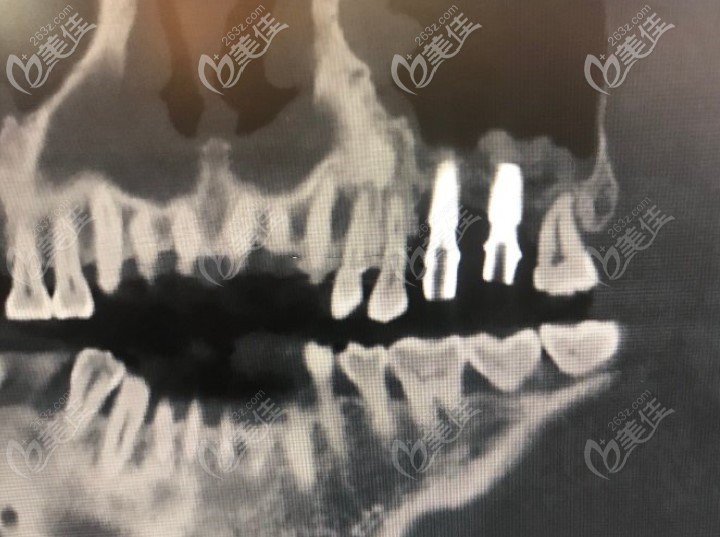

做了两颗牙齿后拍的CT↓↓↓